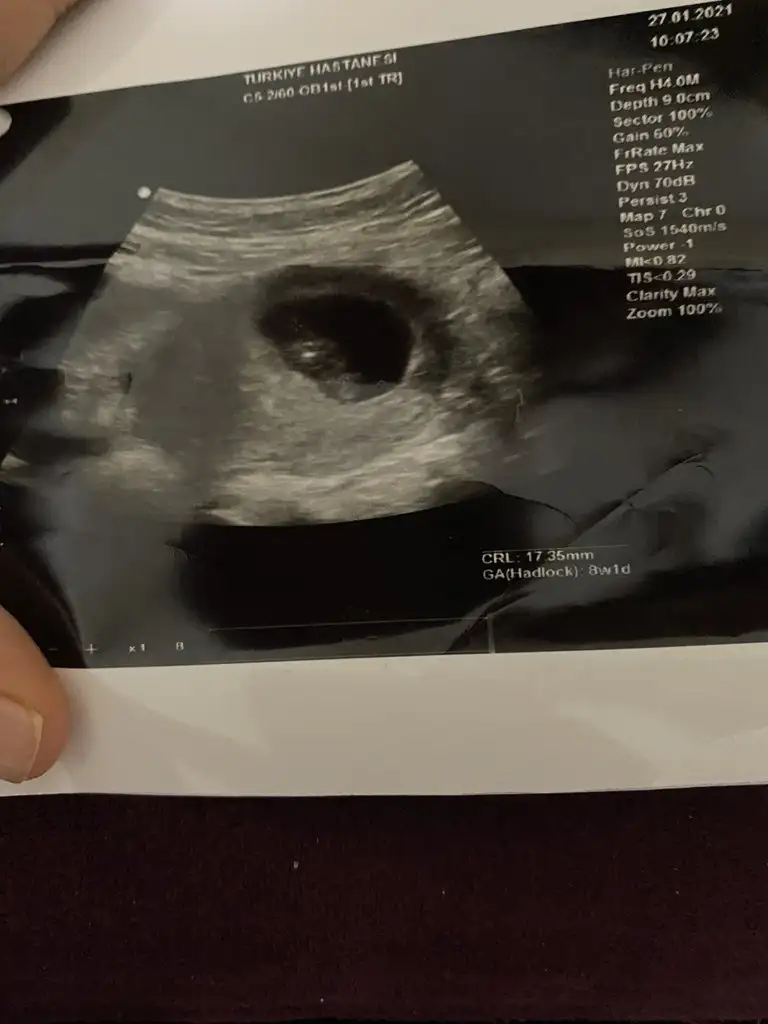

Merhabalar 8+2 de çekilen bu ultrasondan da cinsiyet tahmin edebilecek olan var mıdır